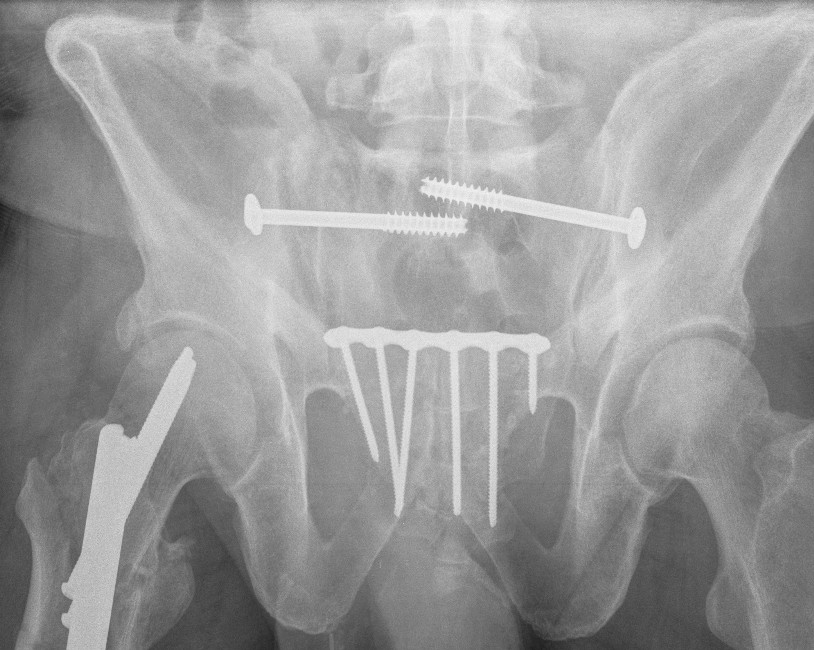

Post-operative XRs: AP, outlet and inlet views

Sacro-iliac screws

Insert 6.5 mm partially threaded cannulated screw, to aid compression

Post operative

Check screw position with CT